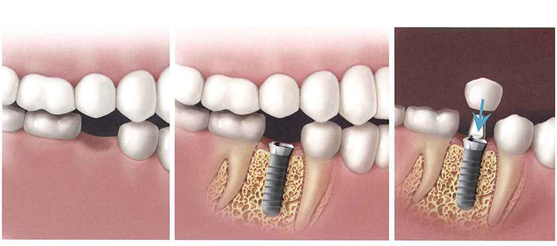

How is the procedure done?

First a comprehensive exam is done to determine a treatment plan. Periodontal treatment may be needed. The first stage involves inserting the implant into the bone in the area of the missing tooth/teeth. After the bone heals and fuses to the surrounding bone, the 2nd stage is planned. An artificial crown is then fabricated and cemented on top of the implant. There is no damage to the adjacent teeth. The treatment period takes about 3-6 months in stages. Implants can be used for as long as 10 – 30 years depending on the care. Dental implants are just one of the many tooth replacement solutions we offer as part of our reconstructive care. Call us today to see if an implant is the best choice for replacing your missing teeth.